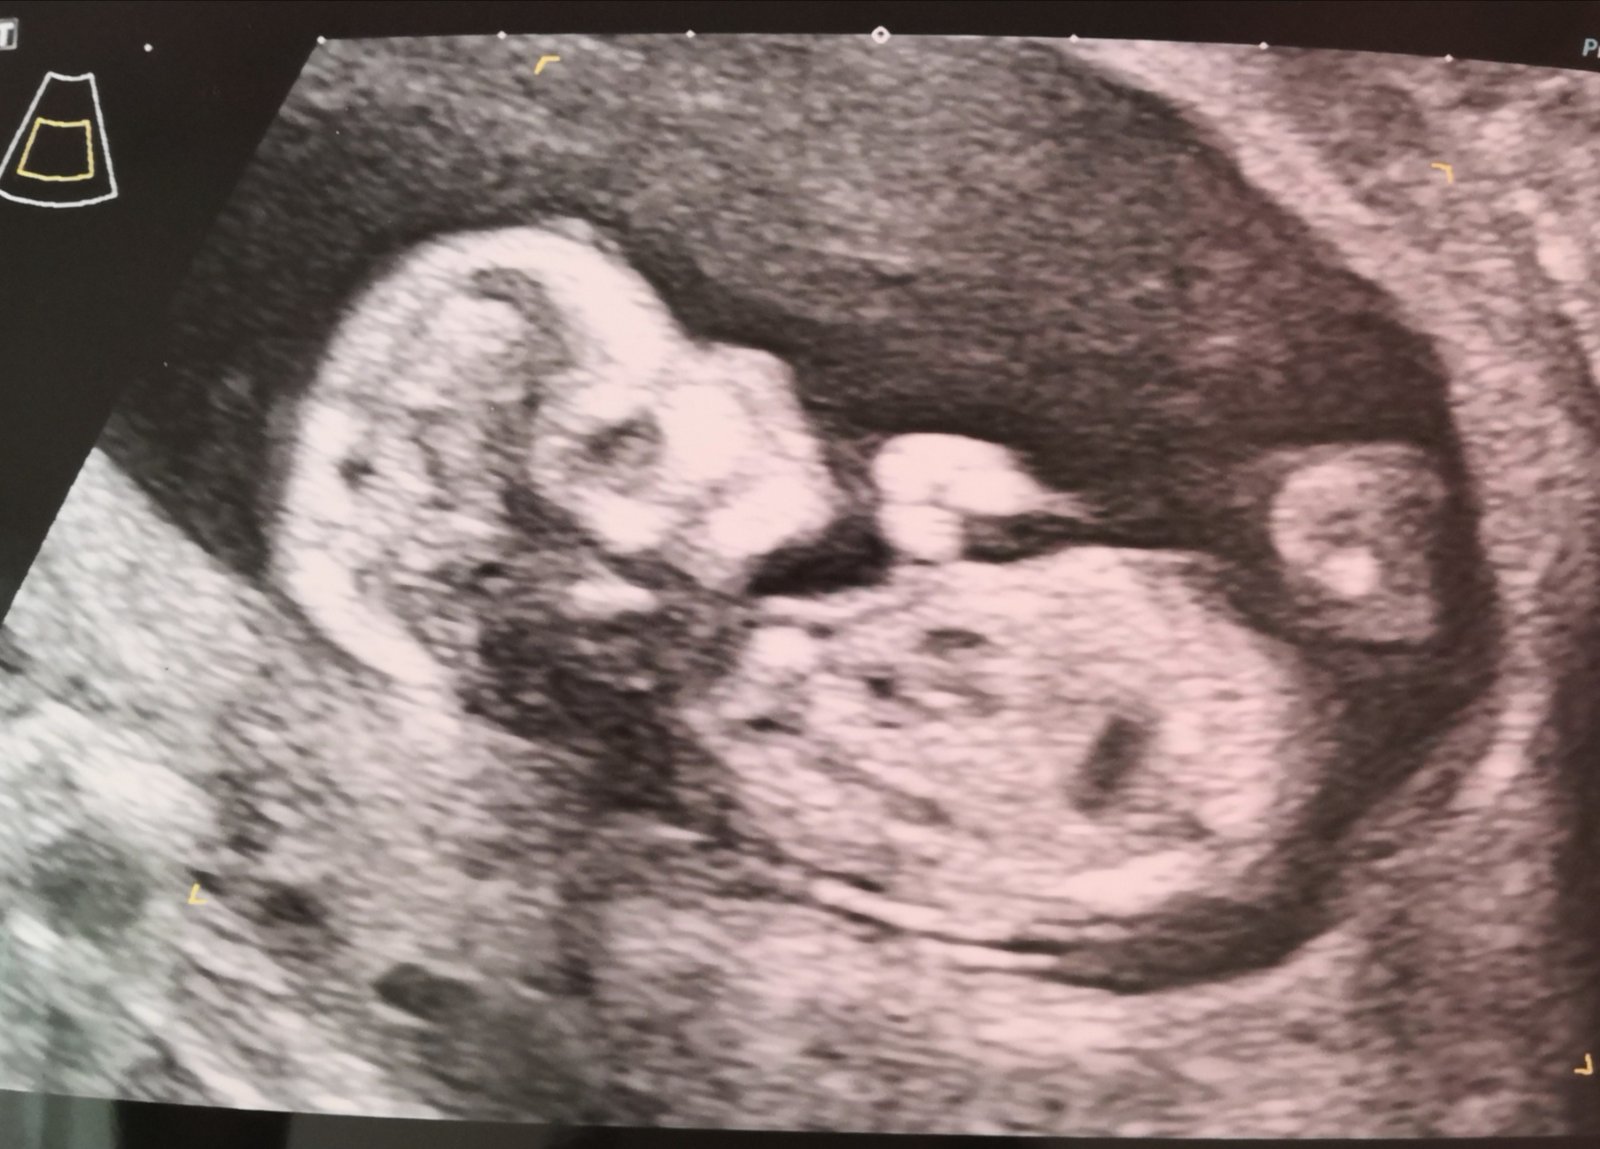

Poznáte pohlaví miminka? Mimčo se nám schovává

Miminko mate krasny, bohuzel nejde vubec nic videt.

Je to miminko....pokud ti nebyl dr schopný říct pohlaví, tak to těžko tady někdo jiný pozná....a z takové fotky už vůbec ne 😁 prostě vydrž 🤣